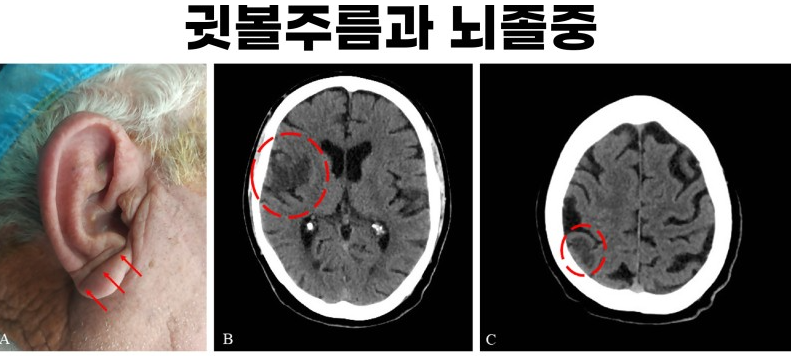

뇌졸중 전조증상 귀주름

뇌졸중 귀주름이란 무엇인가요?

귀주름은 일반적으로 귀와 머리 사이에 생기는 주름 모양의 피부발진을 말합니다. 귀주름은 대개 귀와 머리 사이에 생기며, 발생 시간에 따라 급성 귀주름과 만성 귀주름으로 나뉩니다. 급성 귀주름은 발생 후 1~2일 이내에 사라지지만, 만성 귀주름은 지속적으로 발생하며 피부가 두꺼워지고 검은색으로 변색됩니다.

귀주름은 뇌졸중 전조증상인가요?

귀주름은 뇌졸중 전조증상 중 하나입니다. 귀주름은 뇌졸중 발생 전 몇 주에서 몇 개월 전부터 발생할 수 있으며, 특히 뇌졸중 위험이 높은 사람들에게 주로 발생합니다. 뇌졸중 위험이 높은 사람들은 귀주름이 발생하면 즉시 병원에서 검사를 받아야 합니다.

귀주름 모양이 뇌졸중 전조증상이라는 것은 어떻게 알게 되었나요?

뇌졸중 전조증상 중 하나인 귀주름 모양은 2011년 8월에 발표된 논문에서 처음으로 언급되었습니다. 이후에는 많은 연구들이 이어졌고, 귀주름 모양이 뇌졸중 전조증상 중 하나라는 것이 확실해졌습니다. 뇌졸중 전조증상 중 하나인 귀주름 모양은 뇌졸중 발생 전 2주 이내에 발생하며, 뇌졸중 발생 전에 미리 예방할 수 있도록 조기 발견이 중요합니다.

귀주름 모양이 뇌졸중 전조증상인 이유는 무엇인가요?

귀주름 모양은 뇌졸중 전에 일어나는 혈관의 변화로 인해 발생합니다. 뇌졸중 전에 혈관이 좁아지거나 막히는 등의 변화가 일어나면서 귀주름 모양이 생기게 됩니다. 이러한 혈관의 변화는 뇌졸중 발생의 원인 중 하나이기 때문에, 귀주름 모양이 뇌졸중 전조증상 중 하나라는 것입니다.